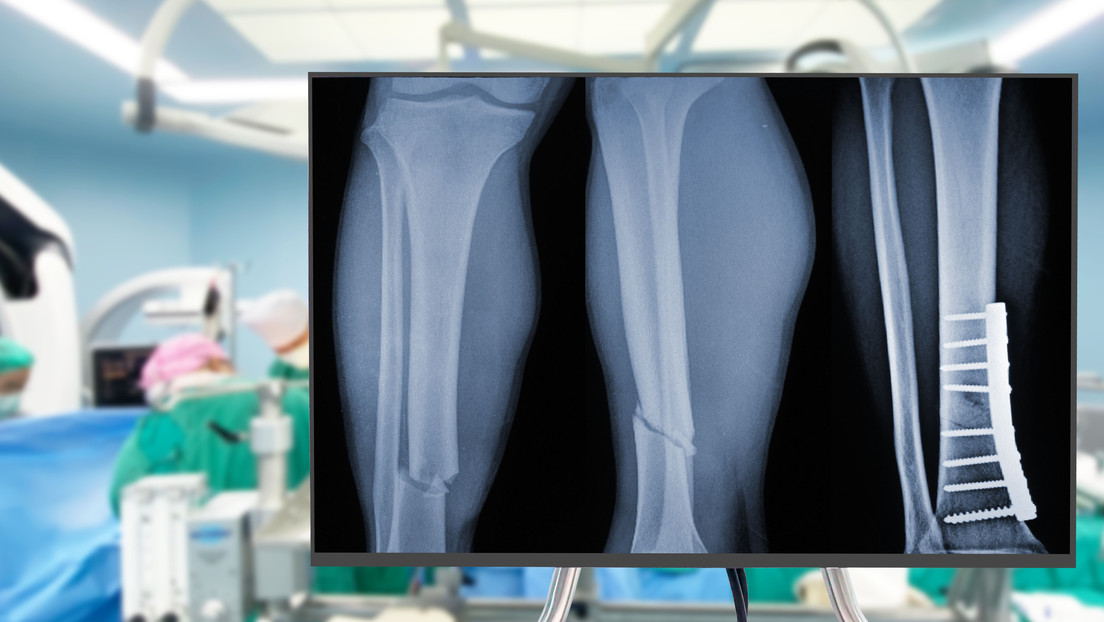

Un grupo de expertos en ortopedia de la provincia de Zhejiang, en China, desarrollaron un pegamento capaz de unir y fijar con precisión fracturas en los huesos en un tiempo de tres minutos.

Esta tecnología adhesiva bautizada como Bone 02, logra unir y fijar en unos pocos minutos distintos fragmentos óseos mediante una incisión de 2 a 3 centímetros que resulta mínimamente invasiva

El material se aplicó a más de 150 personas y en tres meses demostró que favorece un proceso de cicatrización sin complicaciones, con la recuperación total de las funciones de las partes óseas tratadas.

Según la información, este material representa un avance significativo respecto de los procedimientos tradicionales, que utilizan placa